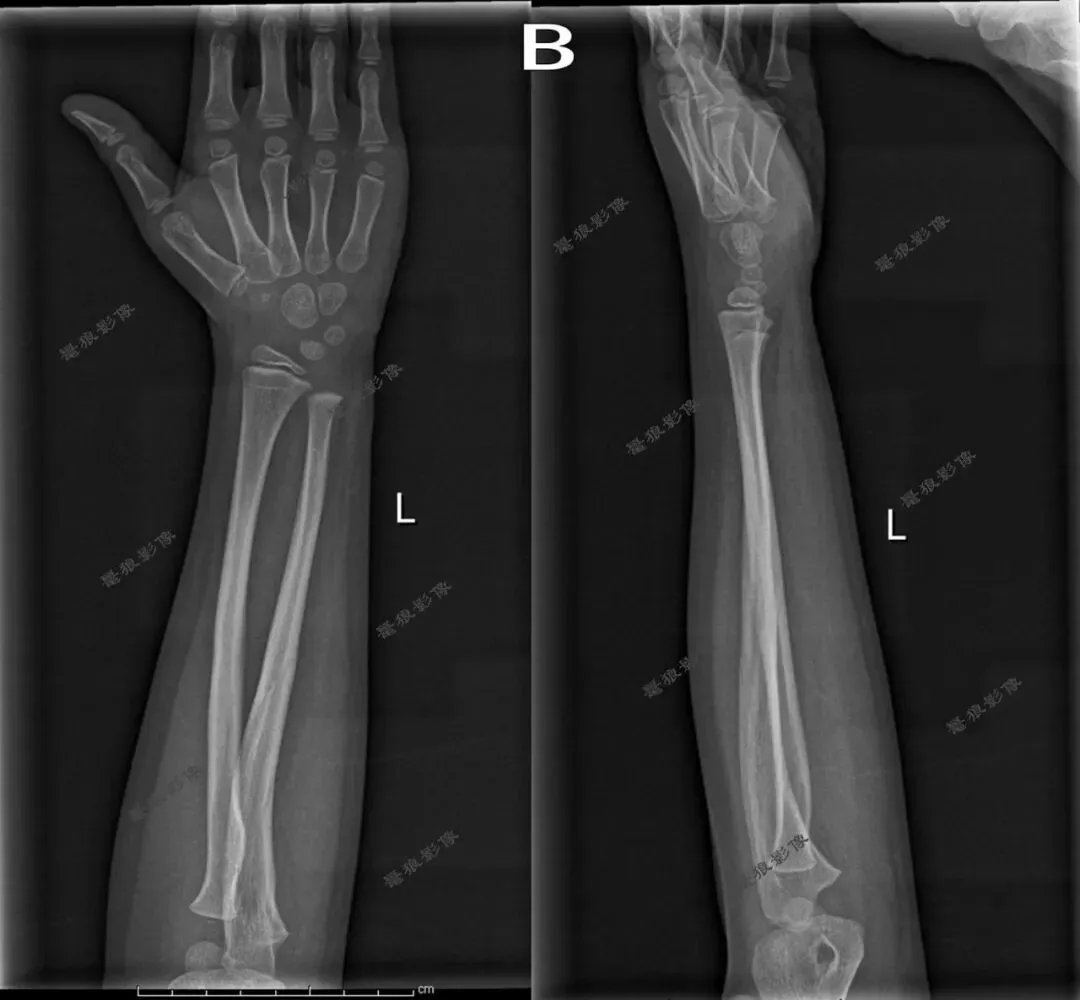

五、桡尺骨侧位

1.摄影要点:

(1)受检者面向摄影台就坐,曲肘约成90°;

(2)前臂呈侧位,尺侧贴近摄影床面,肩部下移,尽量接近肘部高度;

(3)源-像距离为100cm;

(4)中心线对准前臂中点,垂直射入探测器。

2.桡尺骨侧位片标准影像显示:

(1)影像显示桡骨、尺骨、腕关节和(或)肘关节侧位影像;

(2)布局合理,图像包括腕关节和(或)肘关节,至少应包括一个关节,桡尺骨呈侧位影像;

(3)清晰显示骨小梁和周围软组织。